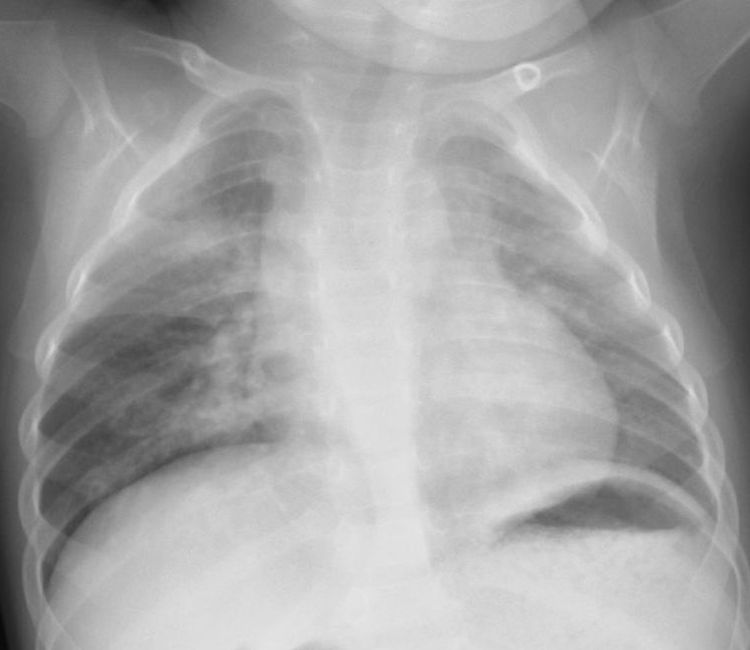

![[27]](https://www.otadragon.jp/cms/wp-content/uploads/2021/11/c35517111-500x383.jpg)

hMPV感染時、CRP 9.1mg/dl WBC 26,200